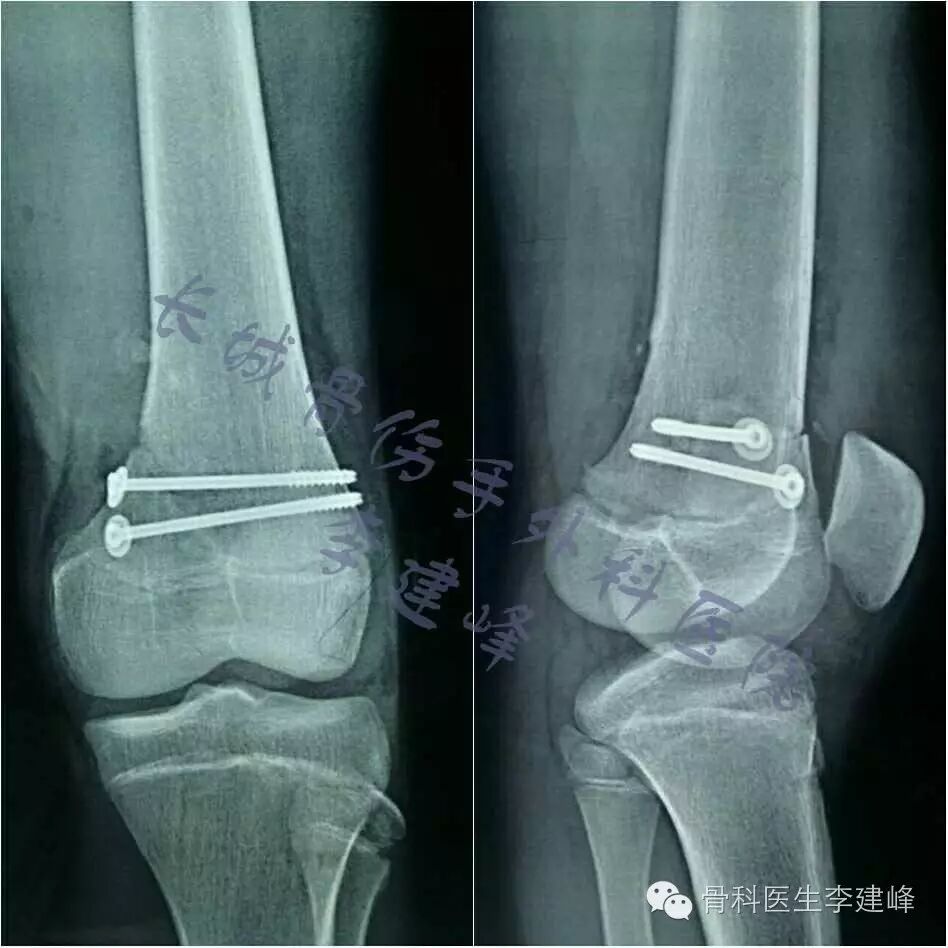

Four case:

术前

术后